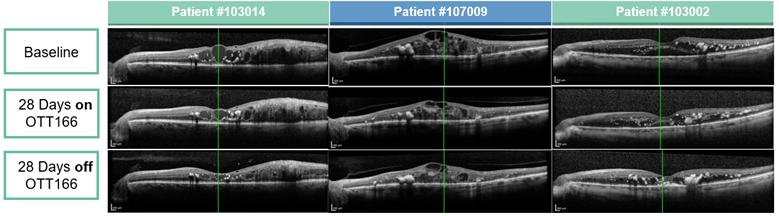

Optical Coherence Tomography (OCT) images from 3 patients with Diabetic Macular Edema (DME) demonstrating Central Retinal Thickness (CRT) improvement and a clear biologic effect of topical OTT-166

Central Retinal Thickness (CRT)µm

Patient #103014 #107009 #103002

Baseline 530   766   404.5

Day 28 327.5 -202.5 (-38%) 570 -196 (-25%) 288.5 -116 (-29%)

Day 56 267 -263 (-50%) 577 -189 (-25%) 243.5 -161 (-40%)

(note: central retinal thickness normal range: 260-280 µm)